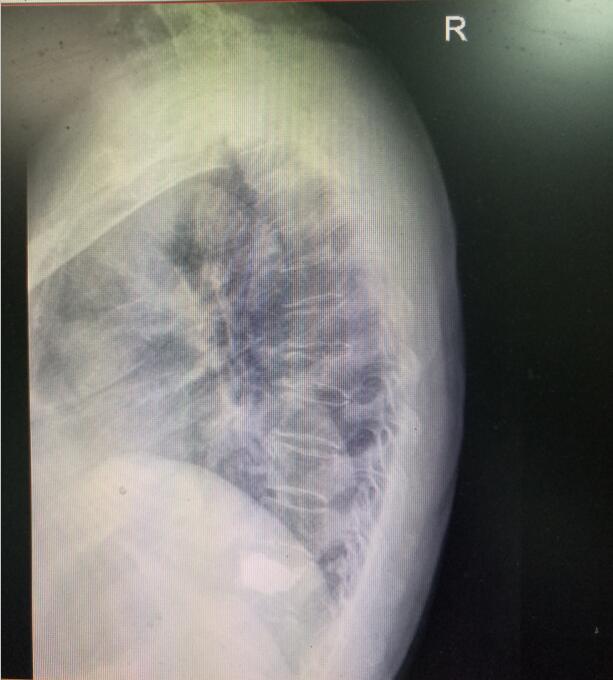

术前DR(数字化的x射线)

术前MRI(核磁共振检查)